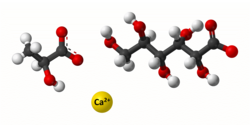

Кальцію глюконат

Бере участь у передачі нервових імпульсів, скороченні м'язів